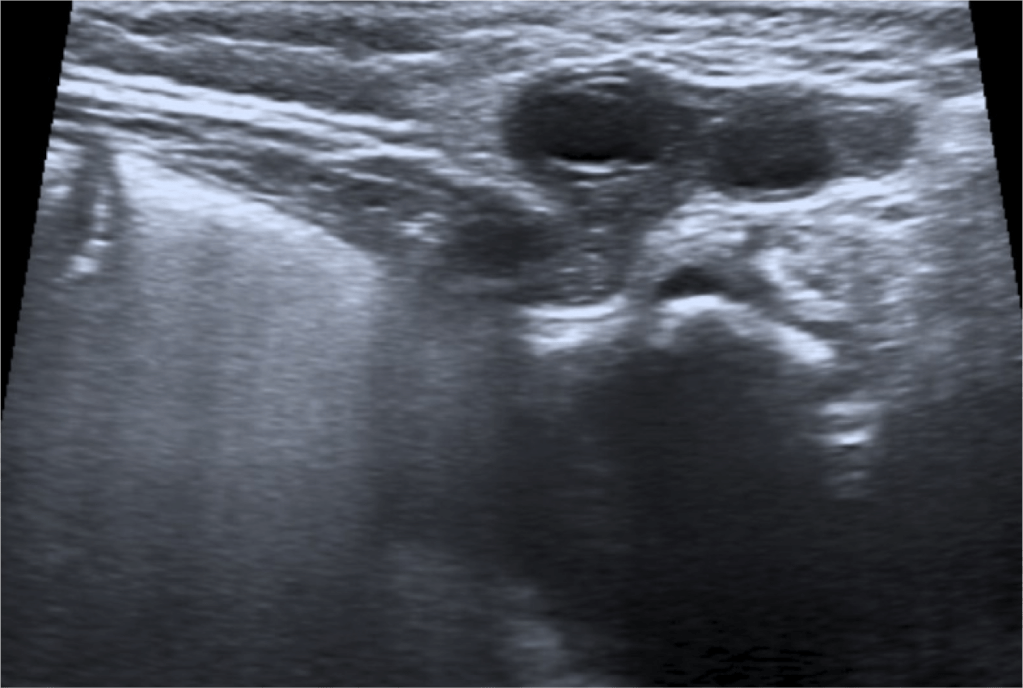

- La ecografía es la técnica de elección (ecógrafo de alta frecuencia)

- El ovario se identifica como una masa con quistes periféricos que representan los folículos.

- La mayoría de estas hernias son de tamaño inferior a 3 cm.

Como ya comentamos, el diagnóstico precoz es importante para evitar que la hernia se complique. Si la torsión del ovario se produce, el compromiso primero venos y linfático y luego arterial produciran a los signos de inflamación , congestión y finalmente isquemia. Los pacientes pueden presentar clínica y signos de irritabilidad, dolor, vómitos, gangrena y necrosis tisular. La imágen ecográfica de torsión ovárica es la de un ovario agrandado con quístes, ecogenicidad heterogénea, sin captación de flujo Doppler color y repercusión de la grasa adyacente.

La morfología del ovario, como ya hemos descrito, es el de una masa que puede o no presentar en el momento del estudio estucturas quísticas periféricas que en la mujer adulta miden entre 15 y 20 mm. Otros autores usan los siguienes términos para referirse a ovarios con estructrucas quísticas:

- Ovario paucicístico: hasta 5 folículos que miden menos de 10 mm

- Ovario multiquístico: más de 6 folículos que miden menos de 10 mm.